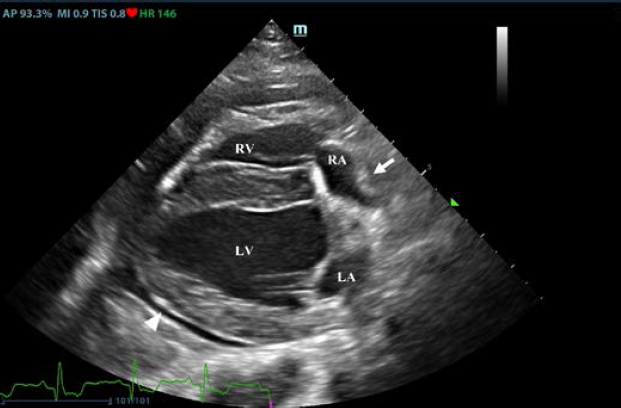

First, transthoracic echocardiogram findings were a small amount of circumferential tamponating pericardial effusion (Fig. 1) and a severe hyperechoic pericardial thickening (10.2 mm) (Fig. 2). The right atrium was normal in size and there was collapse during systole. There was mild septal flattening seen on short axis view of the left ventricle. A short-axis left ventricular M-mode showed posterior displacement of the interventricular septum during late diastole at the time of atrial systole (Fig. 3). The epicardium and pericardium had a hyperechoic appearance with a thin, shaggy layer of heterogeneous echogenic material lining the surface of each (Fig. 1, Supplementary Video I). Pericardiocentesis was not recommended at this time given that the patient was minimally clinically and hemodynamically affected. Few hours later, a second echocardiographic examination, after stabilization of left ventricular volume with intravenous (IV) lactate ringer solution at maintenance rate, showed a worsening of pericardial thickness (13 mm) and an increase in pleural effusion. Furthermore, there was a >25% mitral inflow variation noted with respiration. In addition, there was >30% tricuspid inflow variation with respiration, signs of CP. During the second echocardiography, the patient appeared to be slightly dyspneic due to the increased thoracic effusion.

Fig. 1. Transthoracic echocardiogram – right parasternal long-axis four-chambered view. Note the pericardial effusion, the right atrial collapse (white arrow), the thickened, hyperechoic pericardium, and the scant pericardial effusion (white arrowhead). LA: left atrium; LV: left ventricle; RA: right atrium; and RV: right ventricle.

Supplementary Video I. Transthoracic echocardiogram – right parasternal long-axis four-chambered view. Note the thickened, hyperechoic pericardium, the pericardial effusion, and the hyperechoic appearance of the epicardium and pericardium with a thin, shaggy layer of heterogeneous echogenic material lining the surface of both. The left ventricular chamber appears empty, and the walls are pseudohypertrophic.